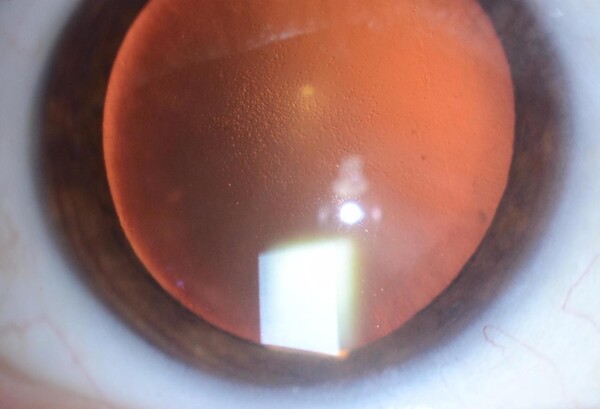

Cuando se pierde un número crítico de estas células endoteliales, el endotelio como un todo empieza a ser incapaz de mantener deshidratada la córnea y empieza a haber edema (líquido) en el espesor de la córnea. Al llenarse el estroma corneal de líquido, la córnea pierde transparencia. Al comienzo de la enfermedad endotelial, el edema suele ser mayor por la mañana, dando visión borrosa que dura alguna/s hora/s y luego mejora con el correr del día. A medida que empora la función endotelial, el edema se hace cada vez mayor, y proporcionalmente progresa la opacidad corneal.

Las enfermedades más comunes que generan edema corneal son: la queratopatía bullosa, donde el daño endotelial está asociado a cirugías oculares previas; la distrofia de Fuchs, donde hay una predisposición genética a una perdida acelerada de células endoteliales; el agotamiento endotelial de trasplantes penetrantes (de espesor corneal completo) previos.

En los pacientes cuyo endotelio falla y la córnea se llena de líquido (edema o descompensación corneal), está indicada la realización de un trasplante endotelial (DSEK por sus siglas en inglés) para restaurar la transparencia de esa cornea. Este trasplante descripto a fines del siglo XX por Melles (Holanda) consiste en la remoción del endotelio enfermo del paciente y su reemplazo por endotelio sano de donante. Para que este trasplante sea efectivo, es condición necesaria que tanto el estroma como el epitelio corneal del paciente enfermo sean normales (que solo esté enfermo el endotelio). Lo novedoso del trasplante endotelial es que, a diferencia del trasplante penetrante, logra una agudeza visual sin corrección mucho mejor y el tiempo requerido para lograrla es menor (2-3 meses vs. 12 meses). Además, desde el punto de vista técnico, es una cirugía menos riesgosa para el ojo ya que se realizan incisiones más pequeñas reduciendo los problemas relacionados a suturas y heridas.